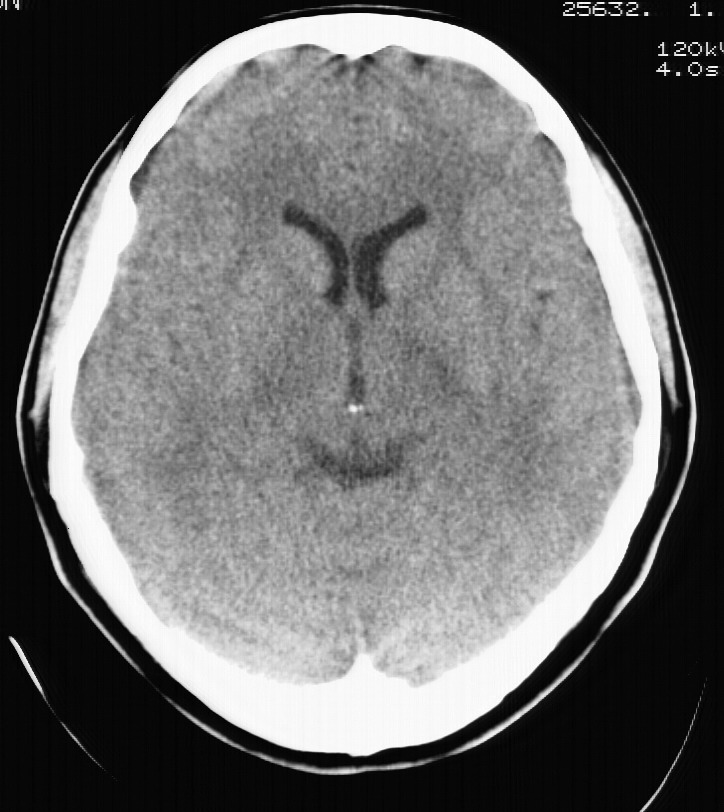

标题: CT5853:右额叶上部占位请会诊

女,34岁,自述头晕胀2年,近期感精神恍惚,无发热,实验室检查阴性。

右顶叶靠近脑表面圆形低密度灶,周围无水肿及占位效应,增强病灶无明显强化,考虑:右顶叶低分级星型细胞瘤。

右额叶上部皮质区见类圆形低密度区,边界不清,无强化,无钙化。

支持大多数战友的意见,1级星形细胞瘤。